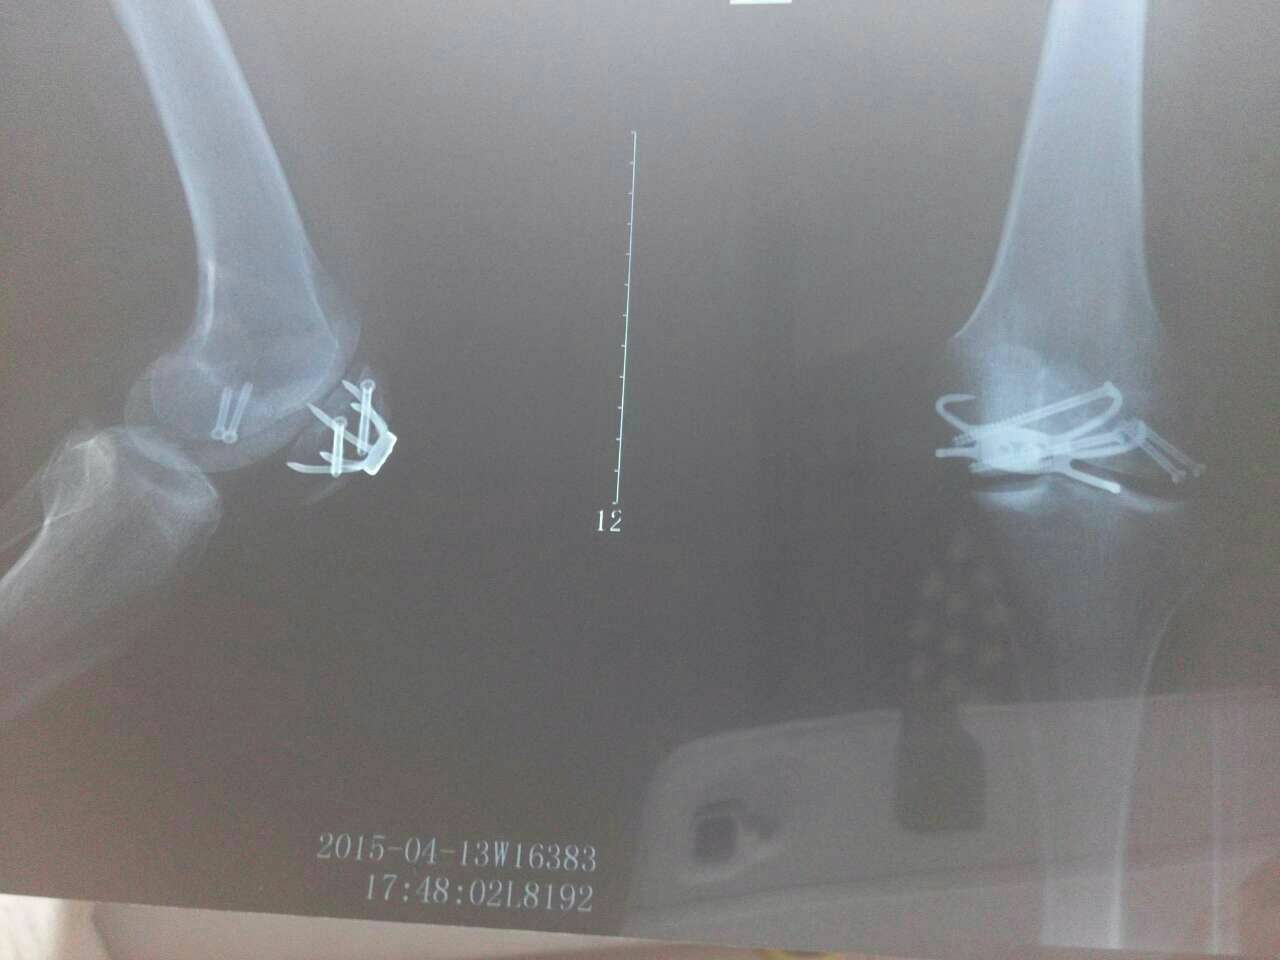

2015年1月24日下午,我和姐姐骑电动车上街,被一辆不按交通行驶的三轮摩托车撞倒,我的左膝盖被三轮摩托车的角铁碰到,造成膑骨开放性骨折,以及膑骨旁边的股骨骨折。

入院后我的主治医生孟辉给我的诊断是:1 开放性膑骨骨折

2 股骨髁骨折

治疗十天开放伤口,确认无感染后于2015年2月4号早上实施内固定手术(膑骨爪+螺丝固定)手术后石膏固定了4周,3月6号拆掉石膏后,膝盖不能弯曲,在医生的帮助下硬扳到60度左右,当时扳的那个疼,相信有经过的人都知道,疼得没有力气去叫了,疼得我当时我就有放弃的想法,实在无法忍受,医生交待了一下就让回家自己练习,回家后,老公就按医生的交待,用红醋洗,中药浴,按摩等等方法,一天到晚不停换着法了用,我也按照医生嘱咐的,天天练,练到没劲,医生说每天除了吃喝拉撒睡就是练习,疼到哭也要练习,这就是我后面每天的经历,哭了练,练了哭,哭得家人不敢看,老公就把门关上,由我在屋里哭着练,练着哭,这难道就是所谓的不放弃吗?我不信也不甘心,我就抹干眼泪上网,找方法,一条条的查看,后来看到一个青云谱为民中医骨伤医院,专治韧带粘连,膝盖不能弯曲的,当时我也没有太相信,还拿给老公看,老公说网上会有真的吗,你还是自己练吧,一句话打了回来,就这样我又重复着哭了练,练了哭的日子,这样狠心着被动压到90,最后我还是崩溃,我再次上网找到青云谱为民中医骨伤医院,细细看了网页,也找上面的患者咨询,后面又去医院的淘宝购药咨询,说明情况后,建议我先拿两瓶试试有效果再买,我也那就试试吧,被骗不就几百块钱吧,如果真的有效,那我就不会这么痛苦了,药品在3.19号收到我迫不急待的按照医院的交待下涂药,贴药,恨不得马上贴上,全部贴上,后来医院又告诉我平时怎么样活动,怎么锻炼,当天晚上用上药,第二天早上腿没有那么硬了,我心里暗暗的高兴,还给自己用药做了记录,来记录我的进步。说的有点多了,给大家看一下我进步的图片,